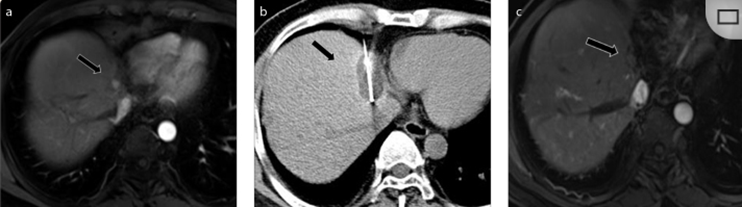

51岁男性患者,肝移植后复发病例

(a) 射频消融后在病变边缘显示残余增强。

(b) 冷冻消融术中影像显示冰球完全覆盖病变。

(c) 19个月后随访,没有发生局部肿瘤进展。